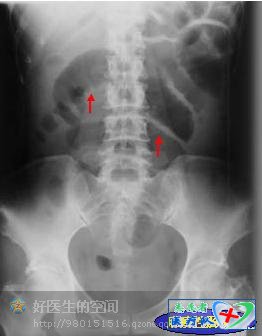

肠管扩张、积气、积液,并见结肠袋,结肠梗阻的特点是梗阻近段的扩张较远离端轻。根据积气扩张的肠管形态可判断梗阻的大体部位,空肠呈鱼肋状,回肠呈光滑管状,结肠可见结肠袋。空肠段以上梗阻为高位肠梗阻,回肠段以下梗阻为低位肠梗阻